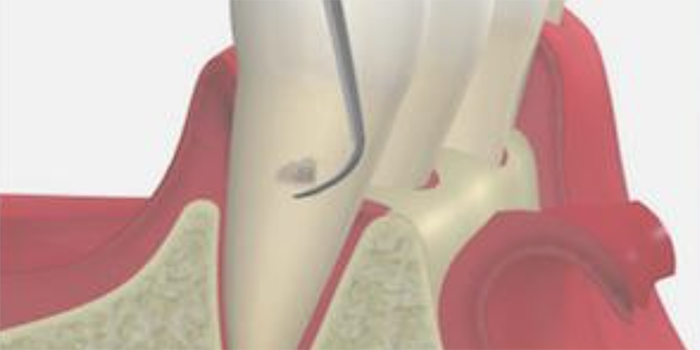

3. SRP

(スケーリング・ルートプレーニング)

専用の器具を使って、歯ぐきの中にある汚れを除去して、歯の根っこ部分の表面を汚れの付着が起こりにくい状態に仕上げる処置です。

主に、歯ぐきの中にまで歯石が入り込んでいる中等度以上の患者さまに対して行います。痛みが強い場合は、麻酔をして行うこともあります。

歯と歯茎の間の汚れをかき出すイメージイラスト